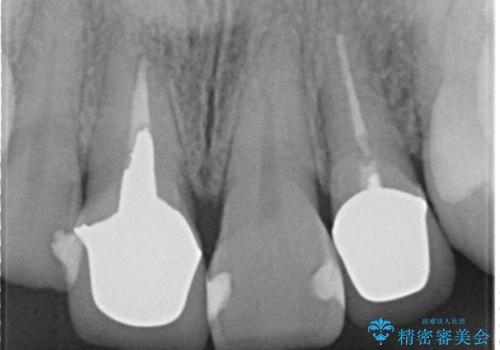

右上1と左上2は再根管治療を行っております。

- 根管治療により痛みや腫れがひかない事や、術後に痛みや腫れが生じる事、治療によるファイル破折やパーフォレーションなどの偶発症、術後の歯根破折を生じる可能性もあります